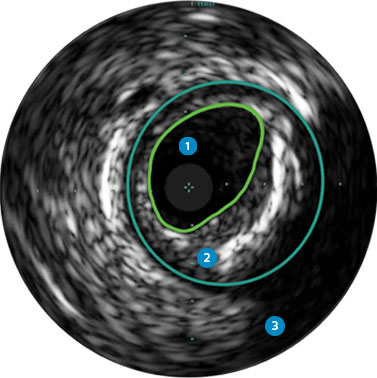

Behandlungsplan Beispiel 1

Lumen

Exzentrische fibröse Plaque mit tiefliegendem Calcium

Schallschatten

Gefässgrösse: 5,5 mm Durchmesser Plaquemorphologie: fibröse Plaque mit intimalem und mittlerem Calcium Plaquegeometrie: exzentrische Läsion Position des Führungsdrahtes: wahres Lumen

Quick-Cross-Katheter: souverän komplexe Morphologien durchqueren Direktionale Atherektomie mit Phoenix: frontal zum Schneiden, Erfassen und Freilegen gemischter Morphologien, einschliesslich Kalzium; Möglichkeit der Richtungssteuerung für grösseren Lumengewinn AngioSculpt Scoring-Ballonkatheter: Calcium messen, um eine Dissektion zu reduzieren4 Stellarex DCB: entwickelt für hohe Leistungsfähigkeit bei Kalzifizierungen